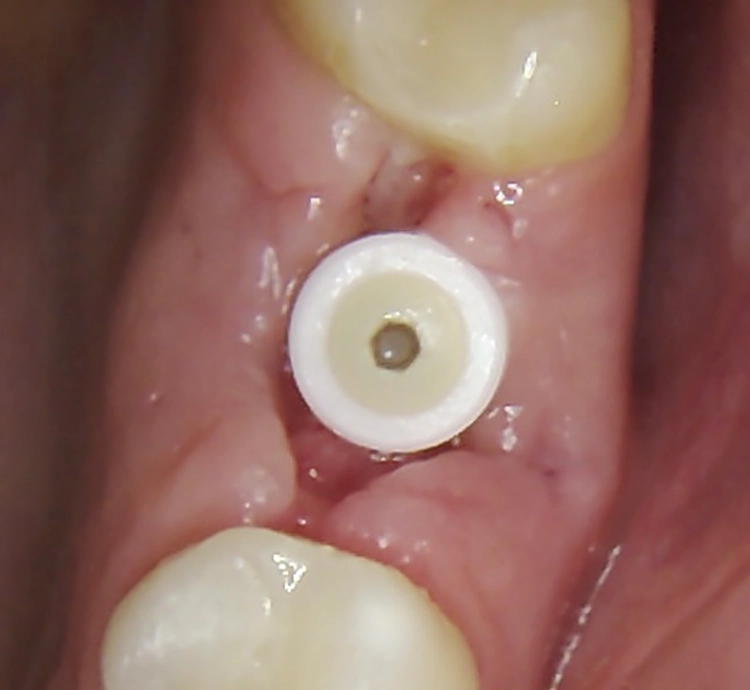

Abb. 2: Repräsentativer Fall von ABH Grad B Septus Typ II. a) Ansichten vor der Installation. Röntgenaufnahme der periapikalen Läsion an einem wurzelkanalbehandelten Molaren und klinische Ansicht der Typ-II-Socket nach der Extraktion. b) Die Ansichten nach der Installation zeigen das Implantat innerhalb des interradikulären Septums und das über dem Implantat platzierte A-PRF. c) Nachuntersuchungen nach 10 Tagen bzw. 2,1 Monaten. Die Röntgenaufnahme zeigt die Knochenbildung zwischen der Sinusmembran und dem apikalen Teil des Implantats. d) Jüngste Nachuntersuchung nach Einsetzen der Prothese.

Abb. 3: Repräsentativer Fall von Grad A Typ I. a) Präoperative Ansicht. Röntgenbild der periapikalen Läsion an einem wurzelkanalbehandelten Molaren. Die Höhe des Alveolarknochens zeigt Grad A an. b) Klinische und radiographische Ansicht der Implantatinsertion unter Verwendung einer Einheilscheibe mit großem Durchmesser (6×8 mm). A-PRF wurde um das Implantat und unter der Scheibe platziert. c) Nachuntersuchung nach 5,9 Monaten vor und nach der Zementierung und Aufbereitung. d) Jüngste Nachuntersuchung nach Einsetzen der Prothese

Die SDS-Zirkoniumdioxidimplantate wurden mit zementierten Pfosten weiter aufbereitet (Abb. 1d, 3 und 4c) und nach 4,74 + 0,95 Monaten Einheilzeit mit endgültigen Kronen versorgt. Die Balkonform ermöglichte ein natürliches Emergenzprofil, das die definitiven Kronen wie die Standardform ausrichtete sowie die Gesundheit des Weichgewebes und die Osseointegration förderte. Bei jeder Nachuntersuchung wurden Stabilität des Implantats, Zustand des umgebenden Gewebes und Vorhandensein von Zahnstein beurteilt.